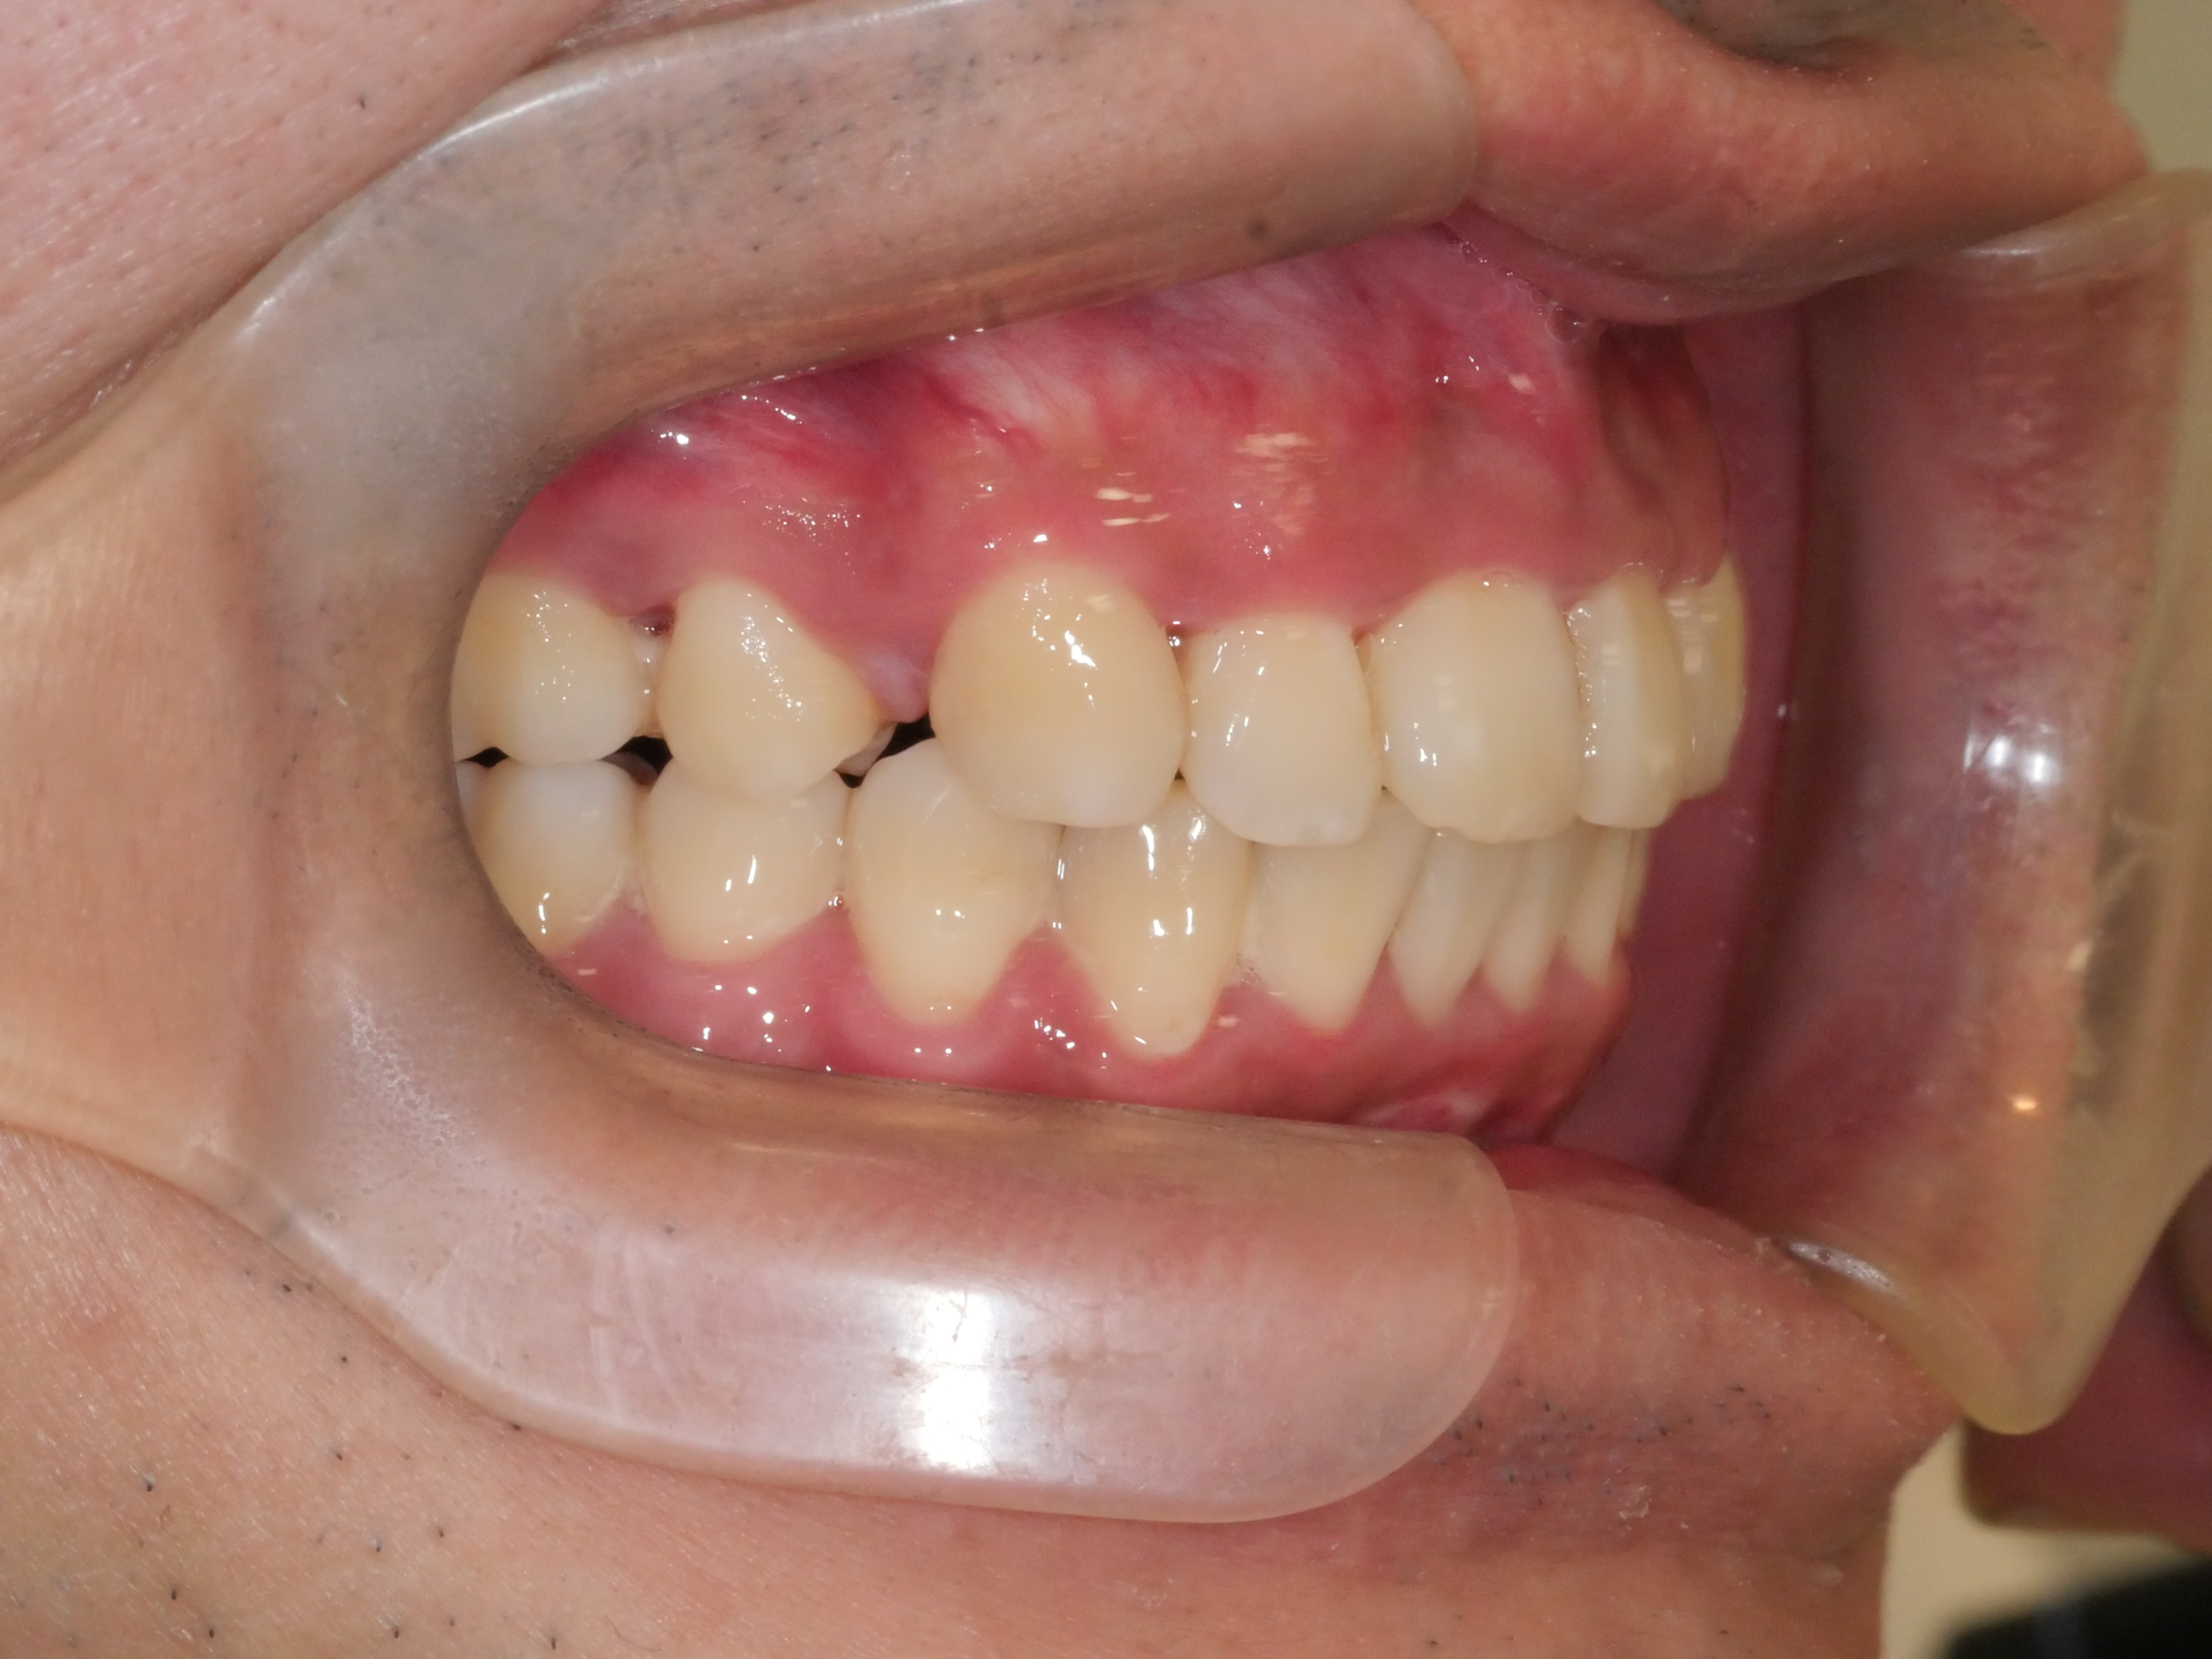

出っ歯を治したい

年齢層 20代

性別 女性

主訴 【主訴】出っ歯を治したい 【診断・症状】上下凸凹、開咬、口元が出てる

治療費用 検査・診断:38,500-/裏側矯正治療:1,397,000-(※全て税込)

治療期間 約2年(26回)

抜歯 有(上4,4)

矯正の装置 裏側矯正(舌側矯正)

副作用、リスク 歯肉退縮,歯根吸収,疼痛,咬合の違和感,装置の違和感,虫歯,歯肉炎

case14_出っ歯_before

Before

case14_出っ歯_after

After